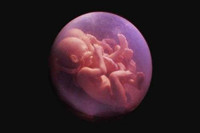

當(dāng)順利進(jìn)入懷孕的三個(gè)月時(shí),此時(shí)的寶寶已經(jīng)由最初的胚胎發(fā)育成型為胎兒了,三個(gè)月時(shí)胎兒的活動(dòng)還并不是很強(qiáng)烈,這也是為什么現(xiàn)在還感覺不到胎動(dòng)的原因。有少部分孕婦此階段還...

在懷孕的9-12周里胎兒寶寶每一周的細(xì)微變化是怎樣子的。接下來,跟隨本文一起走進(jìn)孕三月知識小課堂,讓我們通過懷孕三個(gè)月的胎兒圖,來了解胎兒寶寶的各種細(xì)微變化吧...